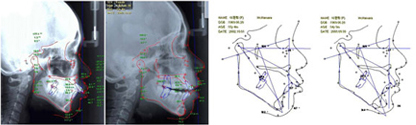

去医院拍摄X光并进行电脑分析,对牙齿进行检查,分析问题点并进行沟通,之后才能制定手术方案。综合的手术方案应该以精准科学的分析为基准,术前,应与患者进行充分的沟通,只有这样才能确保获得满意的手术效果。